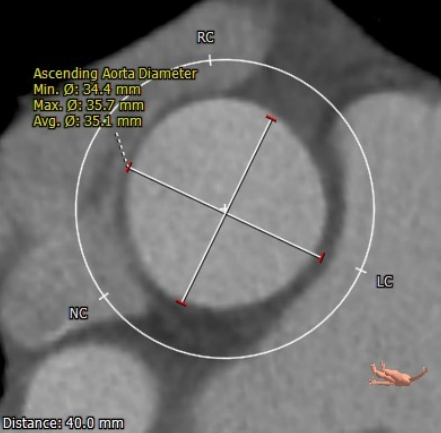

升主动脉